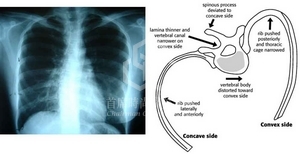

右乳 左乳

大小 小 大

乳頭高低 高 低

乳下線(IMF) 高 (結構發育不良) 低

乳房外緣 內縮 外放

脊柱側彎的模擬嚴重度立體示意圖: 分類主要有二: (1) Thoracic curve type(輕微型); (2) Double major curve type (嚴重型)

脊柱側彎造成軀幹的旋轉效應(trunk rotation), 胸脊柱右曲者較多, 左側胸部較突起+乳房也較大, 左臀也較突出.